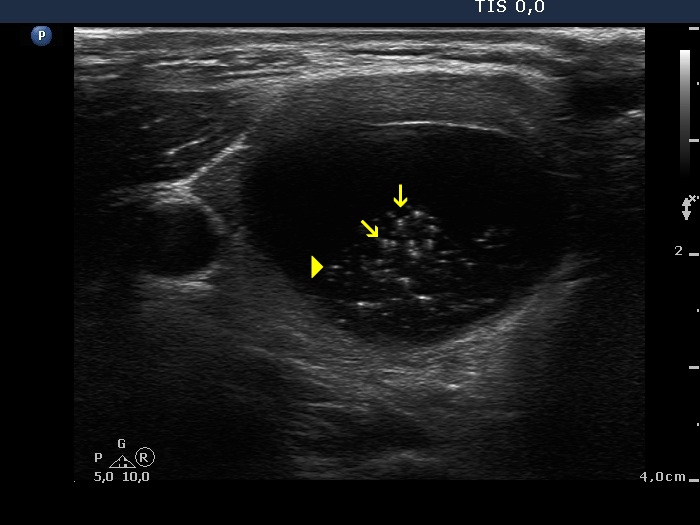

Benign colloid goiter (cytological diagnosis) - case 386 |

At first sight, this pattern mimics the starry sky phenomenon which would be caused by numerous microcalcifications. However, these granules are found in a cystic fluid therefore they cannot be punctate echogenic foci (microcalcifications).